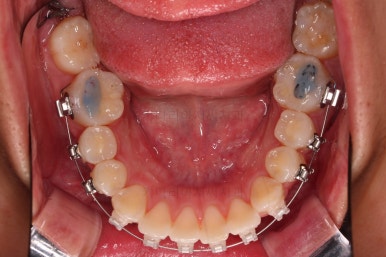

부산연산역치아교정 치료한지 5개월째 사진입니다.

빠른 시일 내에 가지런하게 되었고, 사랑니도 발치를 했으며, 통째로 뒤로 밀어주기 위한 미니스크류 세팅도 끝난 상황입니다.

주기적으로 내원하면서 뒤로 당기는 힘 조절만 해주면 되는 단계입니다.